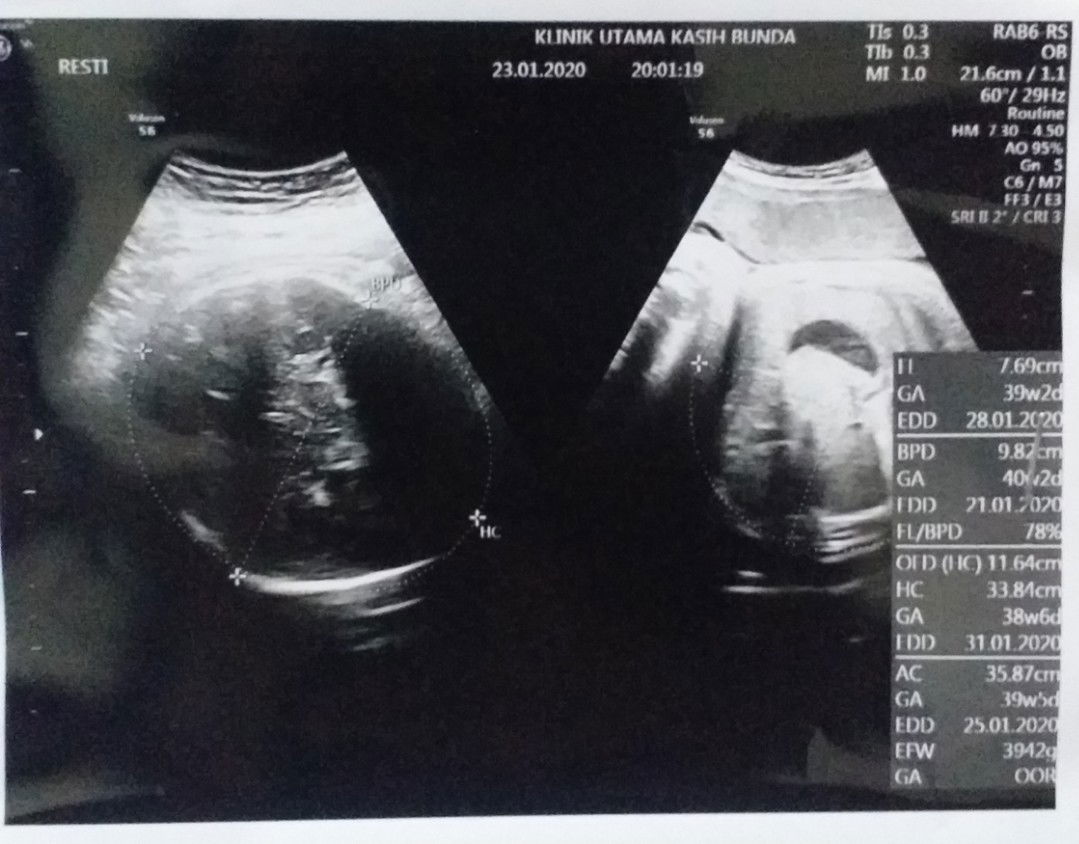

Bayi Tergolong Besar ? Lebih baik normal atau Caesar ? ☹

Selamat pagi bunda~ Sebenernya minggu ini sudah masuk hpl.. tapi blm ada tanda2 dari si dede nih.. Terakhir usg menurut dokter si dede tergolong gede, bb 3,9kg ? kalo ingin normal memang butuh effort yg ekstra.. apakah normal bb bayi segitu bun ? Ada yg bilang faktor bawaan, karna dulu ayahnya wktu lahir aja 4kg, saya 3,5kg, cuma aku jd khawatir aja ☹ jadi bingung normal atau caesar.. mungkin karna mendekati persalinan jadi bawaannya lebih deg2an.. Ikhtiar jalan2, ngepel jongkok, ngerondang udh dilakuin.. cuma pengen cepet2 meluk si dede ☹ Maaf ya bun jadi sharing disini ? Karna sesungguhnya kalo cerita dgn org terdekat pun kadang yg didapat bukan solusi, bukannya menenangkan yg didapat malah perbandingan2 dan segala tetek bengeknya yg ujung2nya kadang bikin down ? Terima kasih, semoga hari2nya menyenangkan ya bunda ??♀️